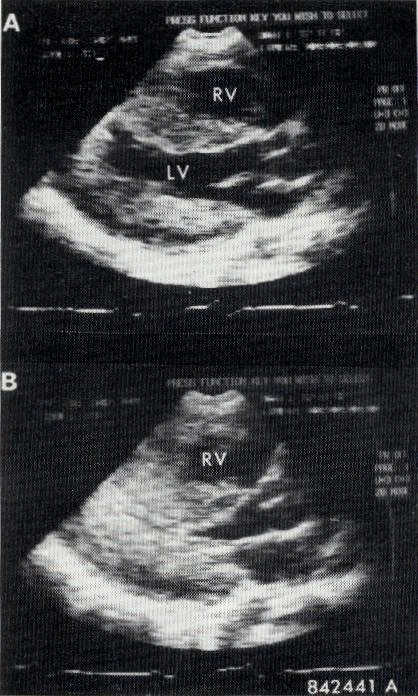

a. Siêu âm hai chiều: đánh giá mức độ phì đại của thành tim. Thường có sự phì đại không đồng tâm của thành thất trái, với ưu thế vượt trội của vách liên thất so với thành sau thất trái. Thất trái thường không giãn và không có các bệnh lý khác có thể dẫn đến tăng độ dày của thành tim. Thành tim có thể dày khu trú từng phần tuy nhiên thông thường có sự dày lan tỏa của tất cả các thành tim, nhất là của vách liên thất. Sự di động ra trước trong thì tâm thu của van hai lá thường gặp được gọi tắt là dấu hiệu "SAM". Dấu hiệu này liên quan đến sự cản trở đường ra thất trái và thường đi kèm với việc đóng sớm van động mạch chủ.

Hình 20-2. Mặt cắt dọc trên siêu âm 2D có phì đại toàn bộ các thành thất trái (LV) trong thì tâm trương (A), tâm thu (B).